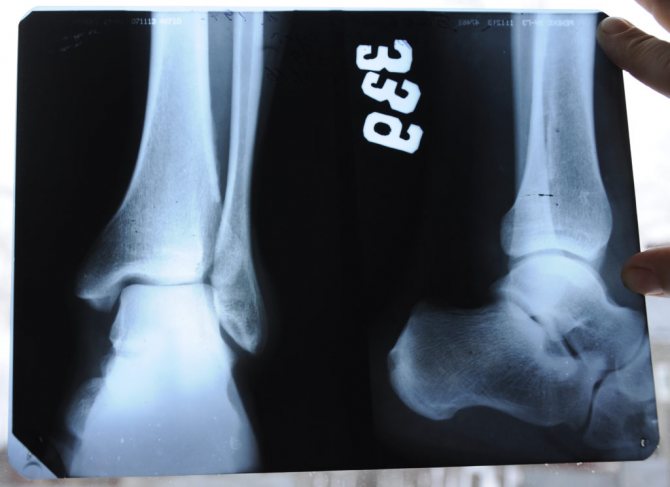

Разрыв связок или перелом голеностопа ― как отличить?

Перелом голеностопа, который возник в результате неударного воздействия, сопровождается разрывом связок. Такого рода перелом кости возникает в том случае, когда поврежденная связка не смогла оторваться от кости и привела к ее перелому.

Наложение схожих друг на друга симптомов перелома и растяжения требует умения отличить эти две травмы. Без рентгена точно поставить диагноз сложно, но для диагностики часто используют метод исключения перелома. Для этого проверяют наличие/отсутствие следующих признаков перелома голеностопа:

Врач не всегда может отличить разрыв связок от перелома во время очного осмотра. Поэтому при появлении сомнений, врач для уточнения диагноза проводит обследование пациента:

- Рентгенография. Самый информативный и доступный диагностический метод, который полностью исключает или подтверждает повреждение костной ткани. Однако эффективность процедуры во многом зависит от грамотности рентгенолога.

Диагноз разрыв связок голеностопного сустава ставится, отталкиваясь от внешнего досмотра больного, его жалоб и данных инструментальной диагностики. Нужно заметить, что в некоторых случаях степень повреждения не сильно воздействует на выраженность симптоматики. Это может зависеть от болевых ощущений больного и механизма травмы. Потому лишь на основании симптомов невозможно провести точное обследование, требуется осуществить глубокую диагностику посредством рентгенографии и МРТ.

Рентгенография должна выполняться в прямой и боковой проекциях. Ее проводят в целях дифференциации разрыва связочного аппарата от перелома сустава либо трубчатой кости. На снимке будет отражено состояние тканей кости. Однако состояние связок он передать не сможет, поскольку мягкие ткани не могут отталкивать лучи устройства, а поглощают. Чтобы исследовать волокна применяется МРТ.